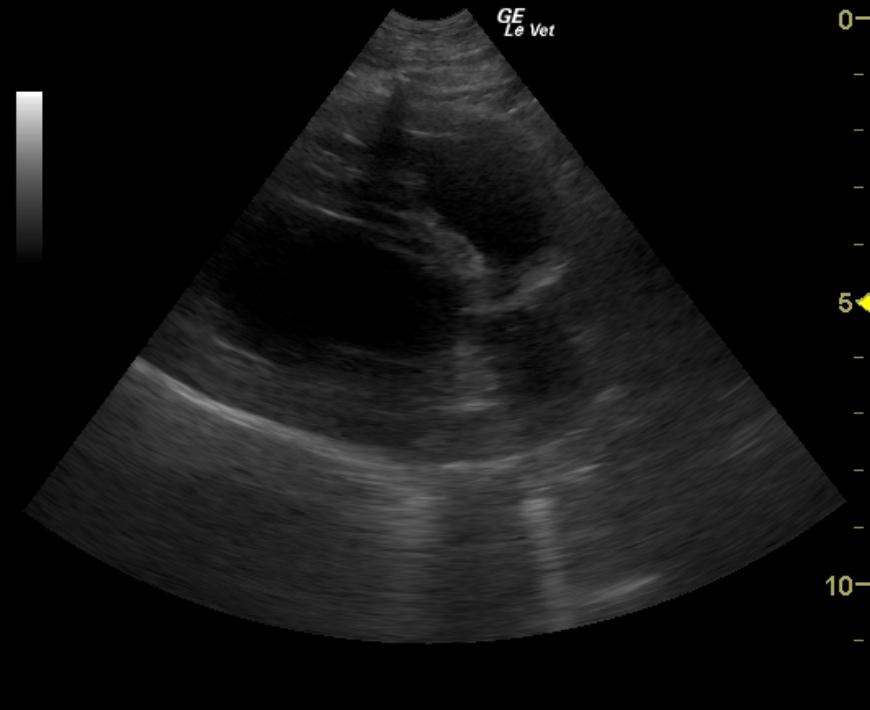

A 10-year-old neutered male Boston Terrier dog was presented for possible seizure activity. A grade II/VI heart murmur and left submandibular lymphadenomegaly were present on physical examination. Abnormalities on CBC and blood chemistry included neutrophilia, eosinopenia, thrombocytosis, elevated ALP activity, and elevated CK. T4 was within normal limits. The patient was treated with enalapril and clindamycin pending ultrasound.